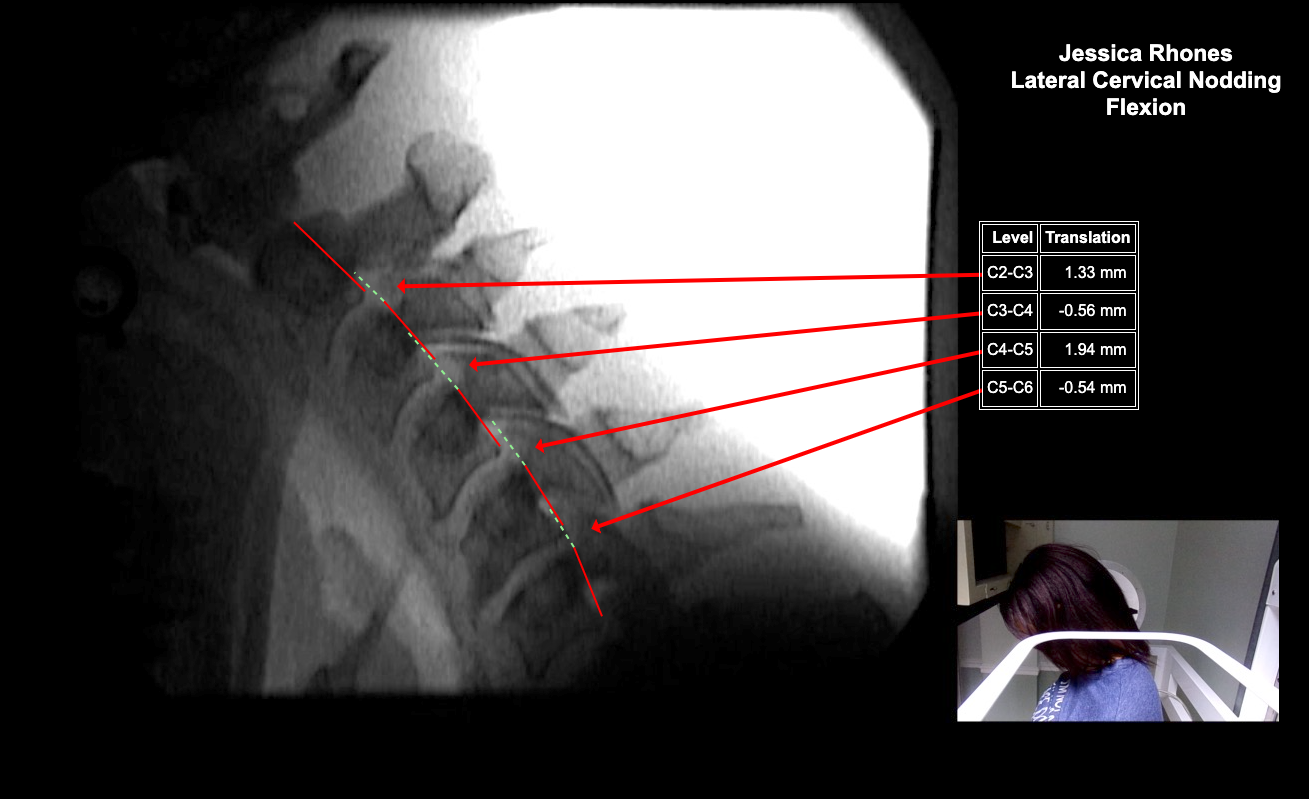

Image 2